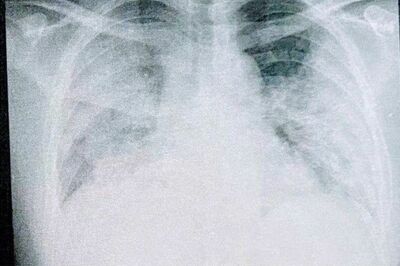

37歳「コロナで肺が真っ白」、医師から “死ぬ可能性” を宣告された男性の痛切な闘病記